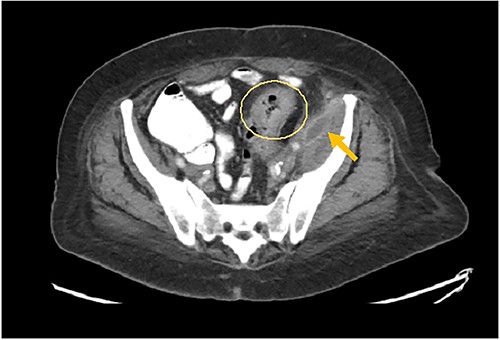

The patient had leukocytosis of 18.23 (Normal: 3.4–11 k/cmm) and CT scan of the abdomen pelvis without Intravenous contrast showed sigmoid diverticulitis with partial resolution of psoas abscess. However, it revealed a tract from the abscess to the hip (Image 3). After a prolonged discussion with the patient, she agreed to proceed with surgical intervention. She underwent exploratory laparotomy. There was a firm, inflamed sigmoid colon densely adherent to the psoas muscle. She also had two loops of small bowel that were densely adhered to the colon. Those loops were removed in block and two small bowel anastomoses were created. After mobilization of the sigmoid colon, there was a defect with fistulization to the psoas muscle. There was a significant amount of purulent fluid coming out of the psoas muscle, which was copiously suctioned and irrigated. Then, an end colostomy was created. A 3 cm elliptical incision was made in the left thigh and the skin was removed. The tissue was probed digitally, and we were able to identify the tract with a significant amount of stool and purulent fluid emanating from the left thigh. Once the cavity was entered, pressure was applied on the thigh, the psoas abscess was draining as well, indicating communication. We drained as much as we possibly could through both the psoas and the left thigh abscess and irrigated them copiously and packed. The patient was hemodynamically stable during the procedure and was extubated and transferred to the floor. The nasogastric tube was removed on post operative day 2, and she started on a diet. Her left hip dressing was changed daily with no signs of further infection. She continued on antibiotics during all hospital stay. She was discharged to Nursing home for physical therapy and adequate wound care. Specimen pathology was negative for malignancy. Patient was successfully reversed 6 months later.

Arrows shows extension of psoas abscess through abdominal wall in the surrounding tissues around the hip. There is not Hip bone involvement. Circle shows abscess next to the hip.